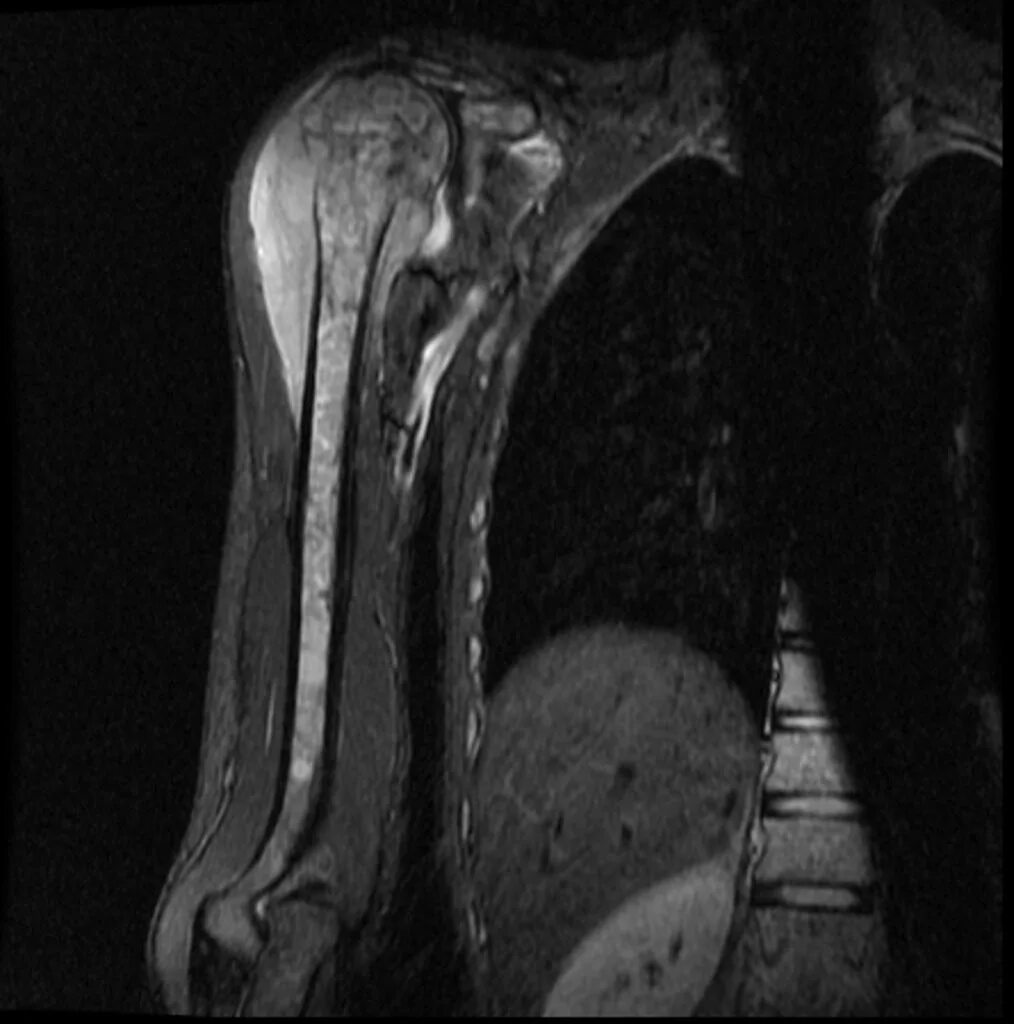

Sarcoma horror